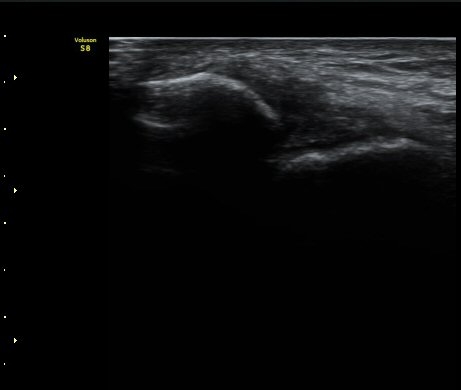

Àü°Å°ñºñ°ñÀδë Á¾´Ü¸é°Ë»ç»ó Àδë ÀδëÀÇ Àú¿¡ÄÚ ºÎÁ¾°ú(±×¸² 3)

ºñ°ñºÎÂøºÎ ¿¬°á¼º ¼Ò½ÇÀÌ °üÂûµÈ´Ù(±×¸² 4).